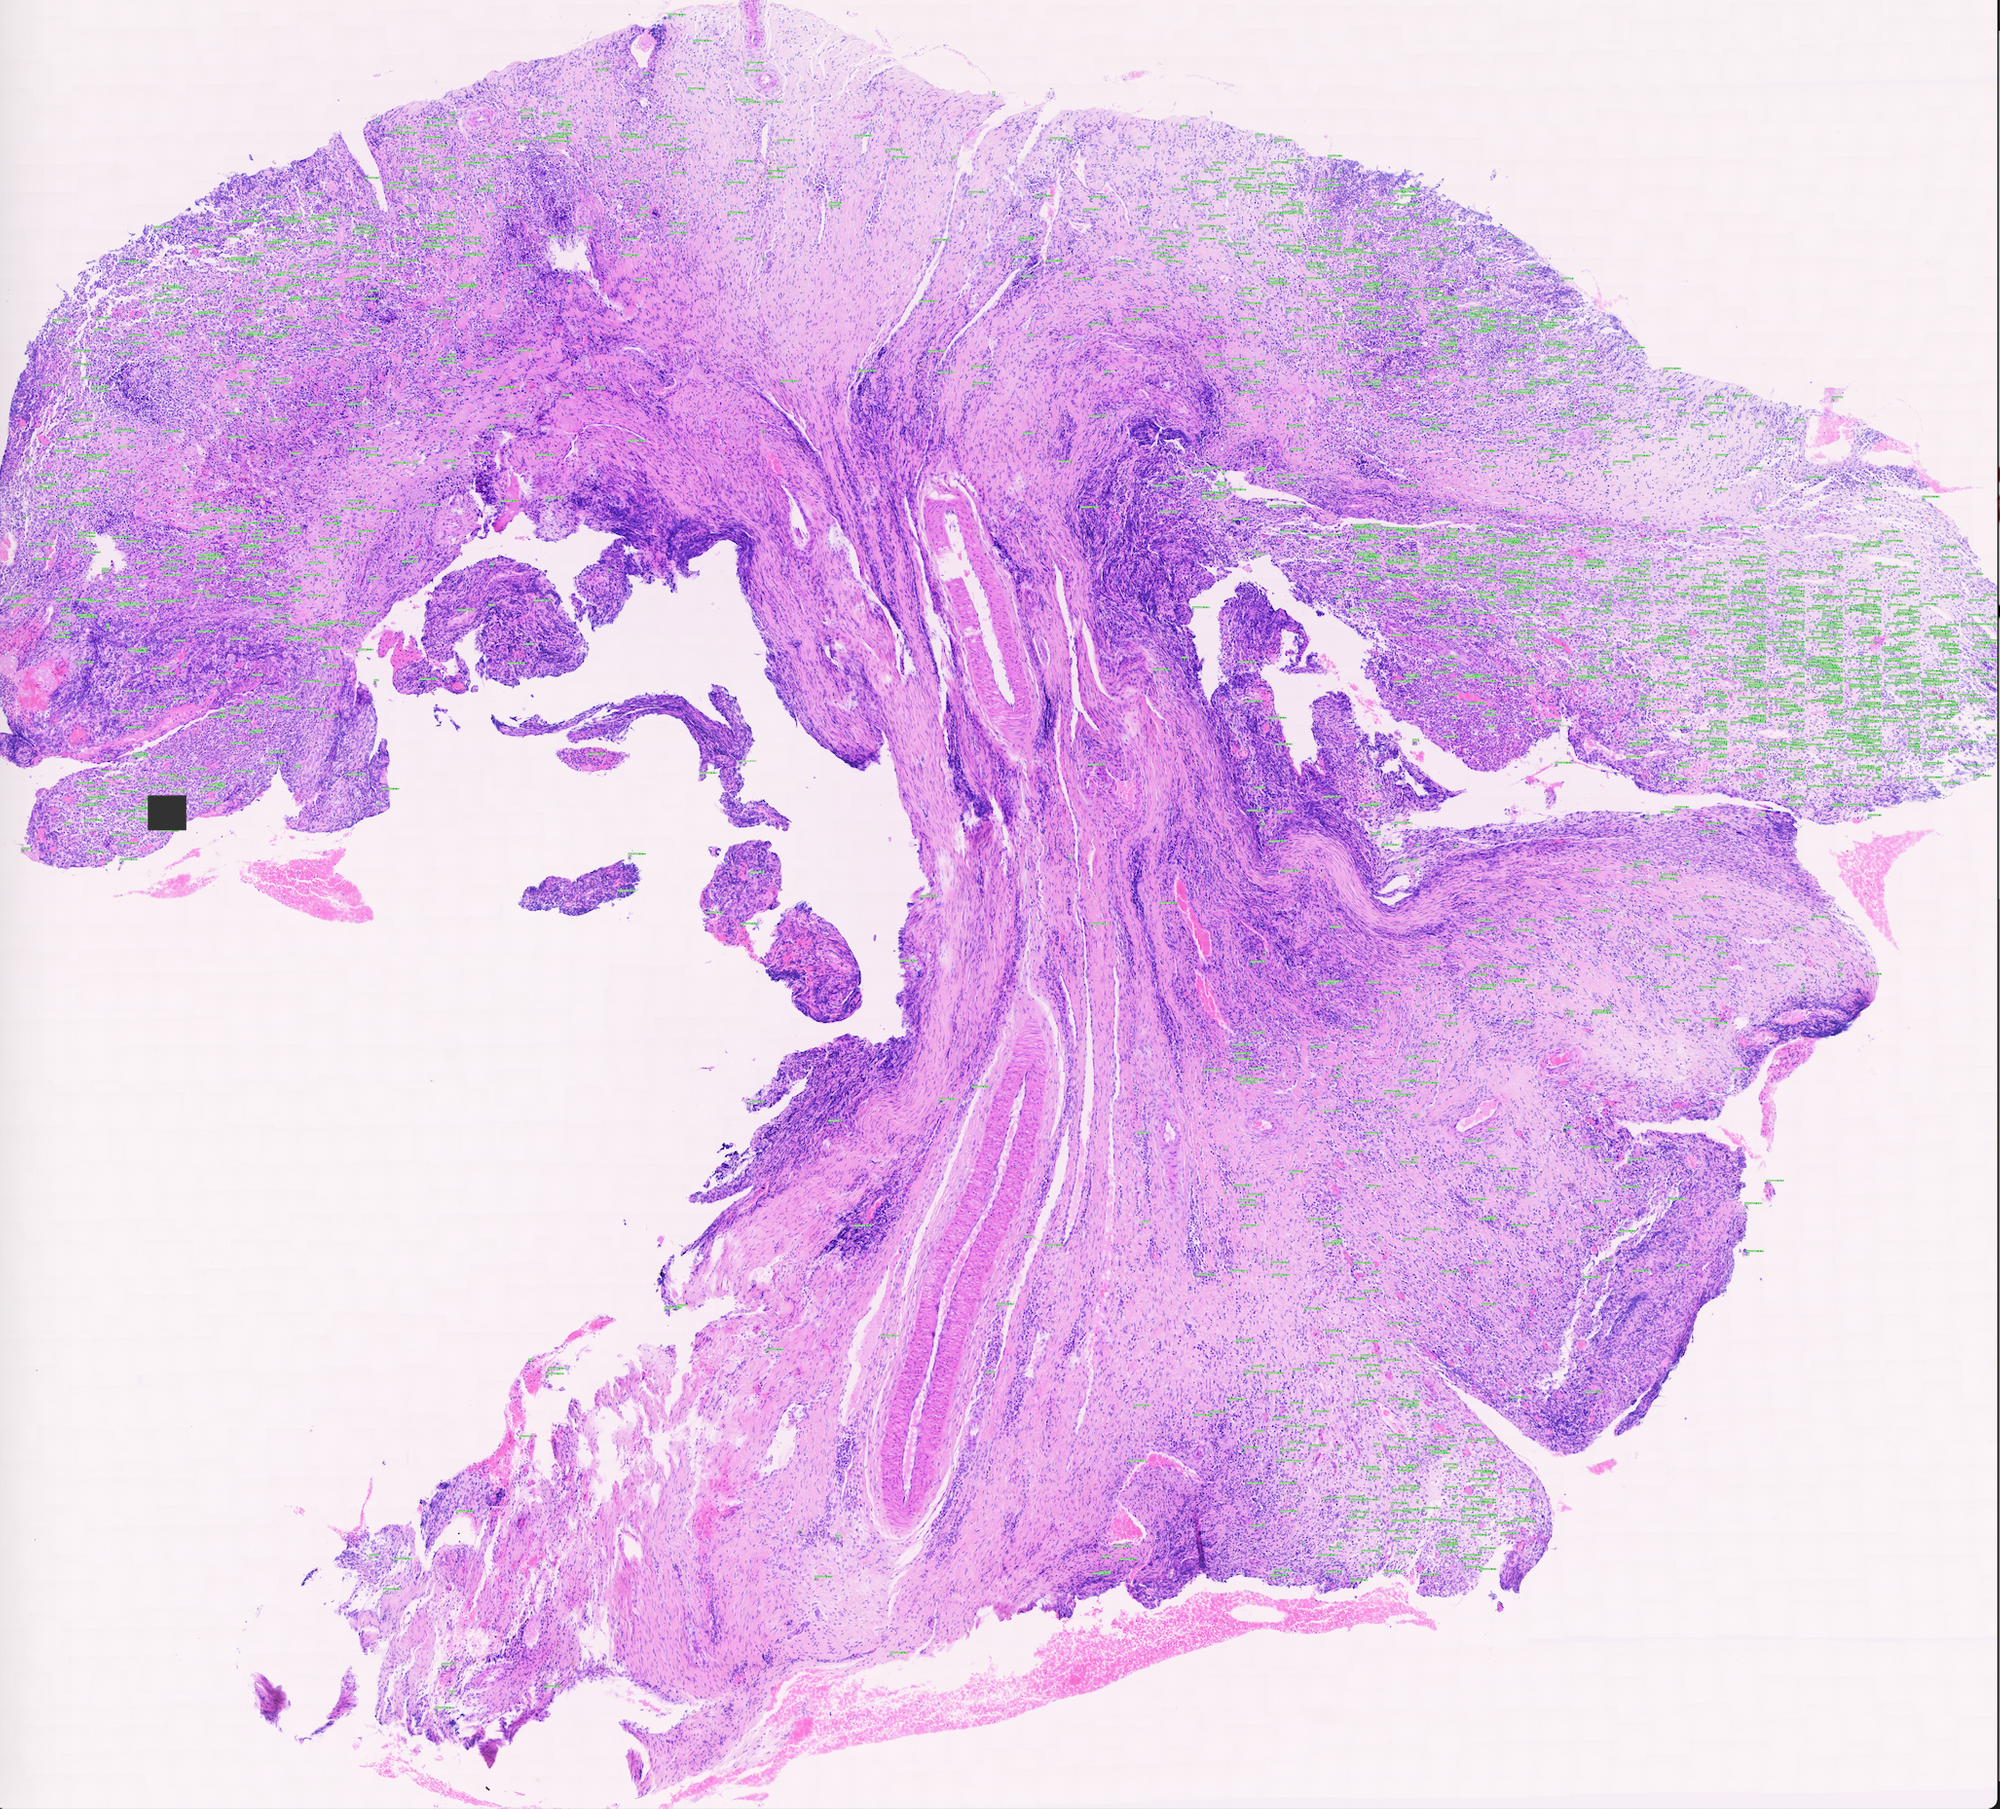

Once each individual tile has inference conducted, the tiles are reconstructed into their 27000 x 27000 pixel final form. The results enable Mateo's team to move more quickly and accurately in determining experiment efficacy.

The output images are truly stunning:

Upon seeing the fully sized image, is it clear why tiling is requisite to capture the detailed granularity necessary for Mateo's team to achieve accurate results!